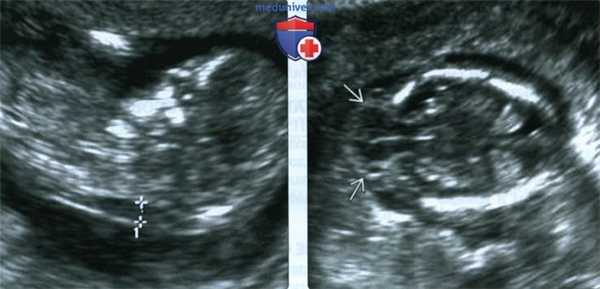

При эхографии в срок 13 недель 3 дня фетометрические параметры плода соответствовали гестационной норме, толщина воротникового пространства составила 1,5 мм; длина костей носа - по 2,5 мм. При трансвагинальном сканировании были обнаружены: затылочное энцефалоцеле размерами 7,4х3,5х3,7 мм (рис. 1), полидактилия кистей (рис. 2), увеличенные кистозно-измененные почки: правая - 28,5х21,3 мм; левая - 26,4х18,7 мм (рис. 3). Объем амниотической полости был нормальным для данного срока.

(Слева) ТАУЗИ плода в I триместре. Определяется умеренное утолщение воротникового пространства (кали-перы). По поводу неровных контуров задней части свода черепа выполнено ТВУЗИ.

(Справа) ТВУЗИ подтверждает наличие дефекта задней части свода черепа, а также затылочного энцефалоцеле крупных размеров, содержащее мозжечок целиком. Показан тщательный поиск других пороков развития.